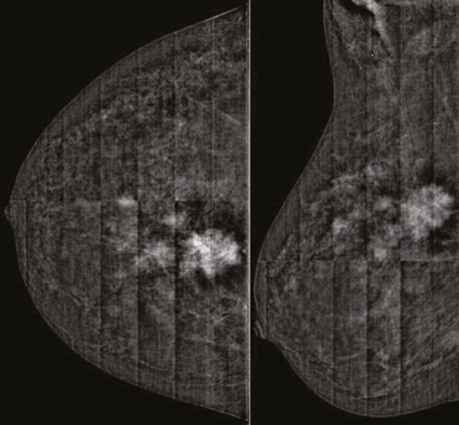

При аналізі контрастованого зображення ділянка гіперфіксації контрасту на 1 год ретромамарно в правій МЗ зменшилася до розміру 20×17×13 мм, значно знизилися щільність та інтенсивність ділянки контрастування. Поряд встановлено лише 1 ділянку аналогічної фіксації контрасту розміром 8×7×5 мм (рис. 9).

Рис. 9. СЕМ з контрастуванням в R-СС- та R-MLO-проєкціях після 8 курсів НХТ. Зменшення таргетного пухлинного вузла, зниження щільності та інтенсивності депонованого конт­расту у вузловому компоненті. Кількість сателітів зменшилася до 1 осередку

На низькоенергетичних сканах таргетне вузлове новоутворення в правій МЗ зменшилося до 17×14×13 мм, значно знизилися щільність та інтенсивність новоутворення, зникла перинодулярна інфільтрація паренхіми. Інших об’ємних новоутворень на площинній мамографії не візуалізувалося (рис. 7).

Рис. 7. Площинна мамографія в R-СС- та R-MLO-проєкціях після 8 курсів НХТ. Зменшилися розмір, щільність та інтенсивність новоутворення, зникла перинодулярна інфільтрація паренхіми